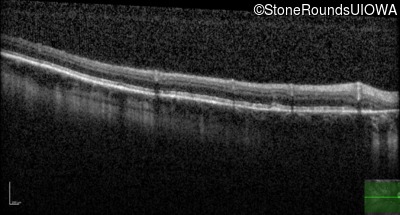

Optical Coherence Tomography - Right - 20/25 -2 sc

Exemplar / OCT Stack